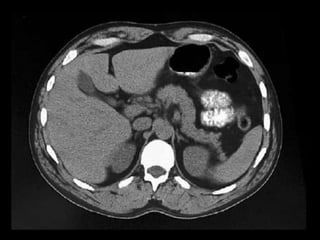

Lipomatose pancreática Irregular

Quando a substituição adiposa é focal ou distribui-

se de modo não uniforme pelo órgão, a condição é

denominada lipomatose pancreática irregular.

Classifica-se em 4 tipos

Diagnóstico diferencial com agenesia pancreática

dorsal e uma massa pancreática.

A região peribiliar poupada e um sistema de

ductos pancreáticos normalmente desenvolvidos à

CPRM permitem o diagnóstico correto.